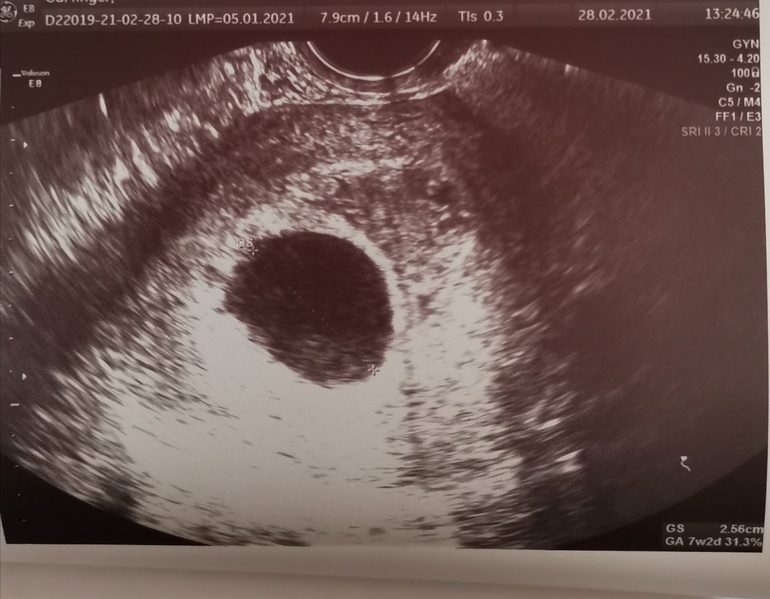

Второе УЗИ как приговор 7+4

Замершая беременностьДевочки, срок по месячным 7+4, сегодня была на узи, анэмбриония😭😭😭 желточного мешка нет, эмбриона нет!

Не спешите,как нет жм,а что за булька в пя? Может аппарат слабый. Повторите через дней 5-7,может ещё все будет хорошо

Людмила

Мария //рожу дочку в 2021//,

Это разве не жм?Может сходить к другому специалисту. В любом случае подождите ещё чуть-чуть

Мария //рожу дочку в 2021//

Везде пишут что при таком размере ПЯ уже ничего не появится(( тем более даже ЖМ нет. На фото видимо так вышло, как ни крутили не было его. Конечно перед процедурой ещё раз УЗИ сделаю, но надежд почти нет